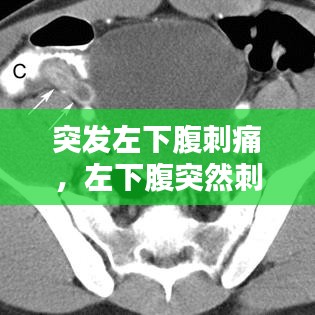

• 影像学检查:如超声波、X光、CT扫描或MRI等,可以提供更详细的内部结构信息。